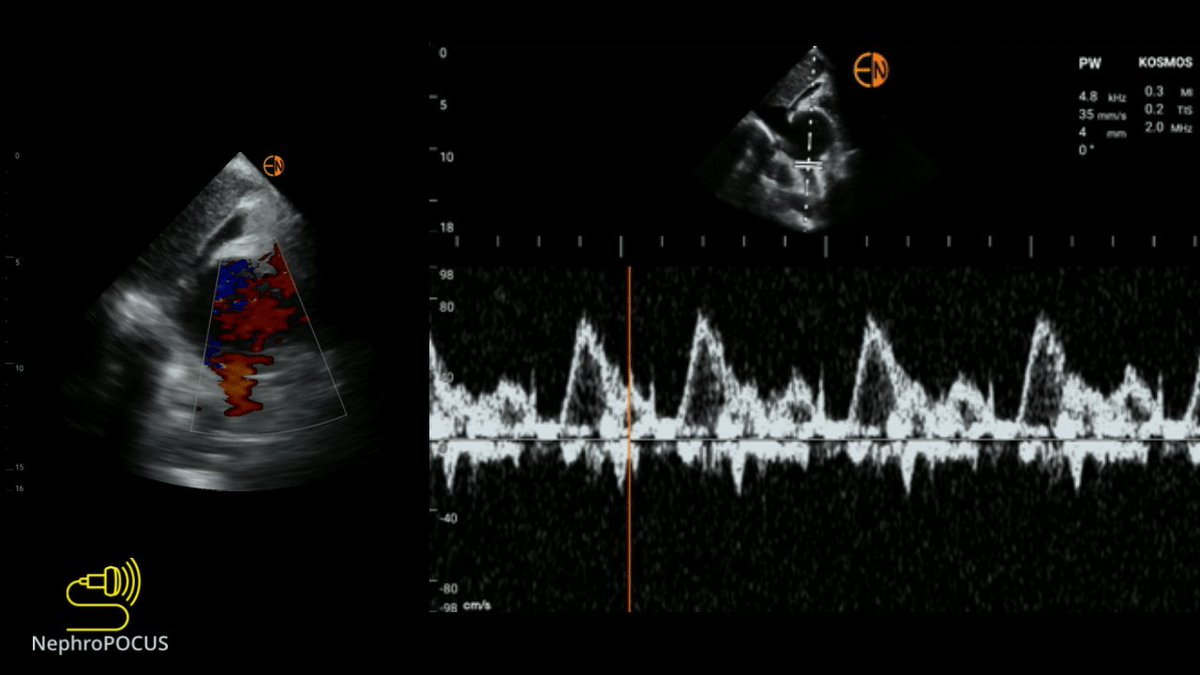

Suprasternal SVC view

Can obtain SVC Doppler (#VExUS) when other views are difficult (e.g. neck collar, RUQ surgical dressings etc)